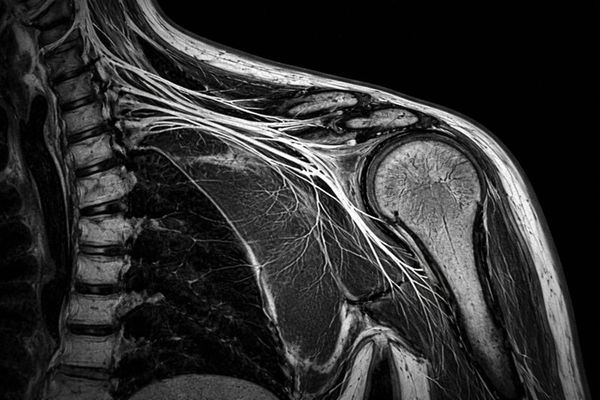

МРТ плечевого сплетения — это современный метод магнитно-резонансной томографии, предназначенный для детального изучения нервных волокон, выходящих из шейного отдела позвоночника и формирующих плечевое сплетение. Метод основан на воздействии магнитного поля и радиочастотных импульсов, что обеспечивает высокую контрастность мягких тканей без лучевой нагрузки. Исследование подходит для пациентов разного возраста и широко используется в неврологии, травматологии и ортопедии.

Исследование дает возможность визуализировать:

• повреждения и разрывы нервных волокон;

• признаки невритов и плекситов;

• опухоли и кисты нервной ткани;

• компрессию нервов окружающими мышцами и связками;

• посттравматические изменения;

• последствия хронических нагрузок и воспалений.

Благодаря высокой детализации МРТ плечевого сплетения помогает выявить патологию даже на ранних этапах, когда клинические проявления минимальны.